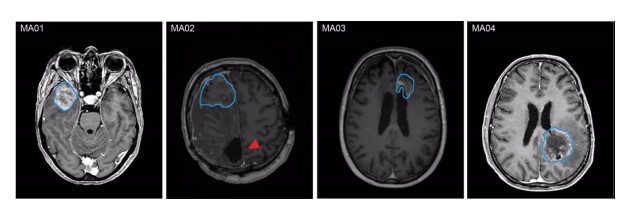

MA01-03為WHO Ⅳ級(jí)IDH野生型膠質(zhì)母細(xì)胞瘤;MA04為WHO Ⅳ級(jí)星形細(xì)胞瘤IDH突變體。

圖1 不同患者M(jìn)RI